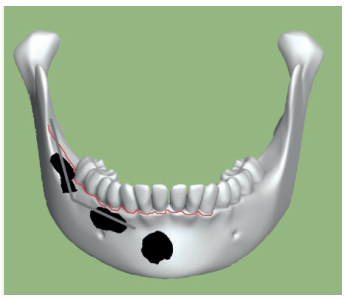

Acudió a servicio de cirugía oral, derivado por su odontólogo, un paciente varón de 65 años sin antecedentes médicos de interés, tras comprobar un importante crecimiento de una imagen radiotransparente respecto a última radiografía de hacía 5 años. El paciente no refirió sintomatología asociada. A la exploración extraoral no se apreció ningún tipo de deformidad ni afectación ganglionar. A la exploración intraoral pese a que se constató la integridad de las corticales, las cuales no estaban abombadas, sí que se pudo apreciar a la palpación un signo positivo de Dupuytren o de “Ping-Pong”. Además se constató una falta de afectación de los dientes del cuarto cuadrante que no presentaban movilidad y tenían una vitalidad positiva (Figura 1). Como complemento a la exploración clínica se solicitó un estudio mediante TAC, donde se apreció la extensión de una lesión radiotransparente que afectaba a rama y cuerpo mandibular derecho. (Figuras 2 y 3).

La cirugía se planteó bajo sedación y con el doble objetivo de la eliminación completa de la lesión con el cordal asociado y evitar un debilitamiento excesivo de la mandíbula. Para ello, se realizó un triple acceso a la lesión que nos permitiese por un lado despegar el quiste en toda su extensión mediante el uso de periostotomos y cucharillas de legrado, y por otro lado preservase una serie de “arbotantes” óseos que a su vez permitieran la posterior colocación de una mini placa desde la rama mandibular hasta el cuerpo, que actuase como refuerzo estructural (Figura 4).